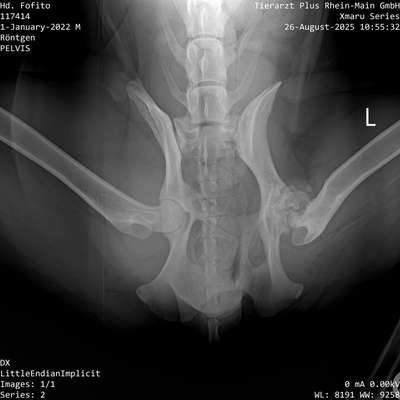

Hallo miteinander 🙂 habt ihr schon mal so eine schlechte Hüfte gesehen? Ich sage immer, mein Hund mit ohne Hüfte. Das betroffene Bein nutzt er quasi nur als Stütze, es ist deutlich weniger bemuskelt als die andere Seite. Er kann sich auch nicht auf die betroffene Seite legen,. Aber kann rennen und toben wie jeder andere Hund. Eine OP ist nicht möglich, da der Knochen so dünn ist, dass kein neues Gelenk halten würde. Bei kleineren/ leichteren Rassen gibt es noch die Möglichkeit den Femurkopf zu entfernen. Aber davon haben uns 3 Tierärzte abgeraten, da Fito mit seinen 43 kg zu schwer wäre. Hat jemand damit Erfahrung?